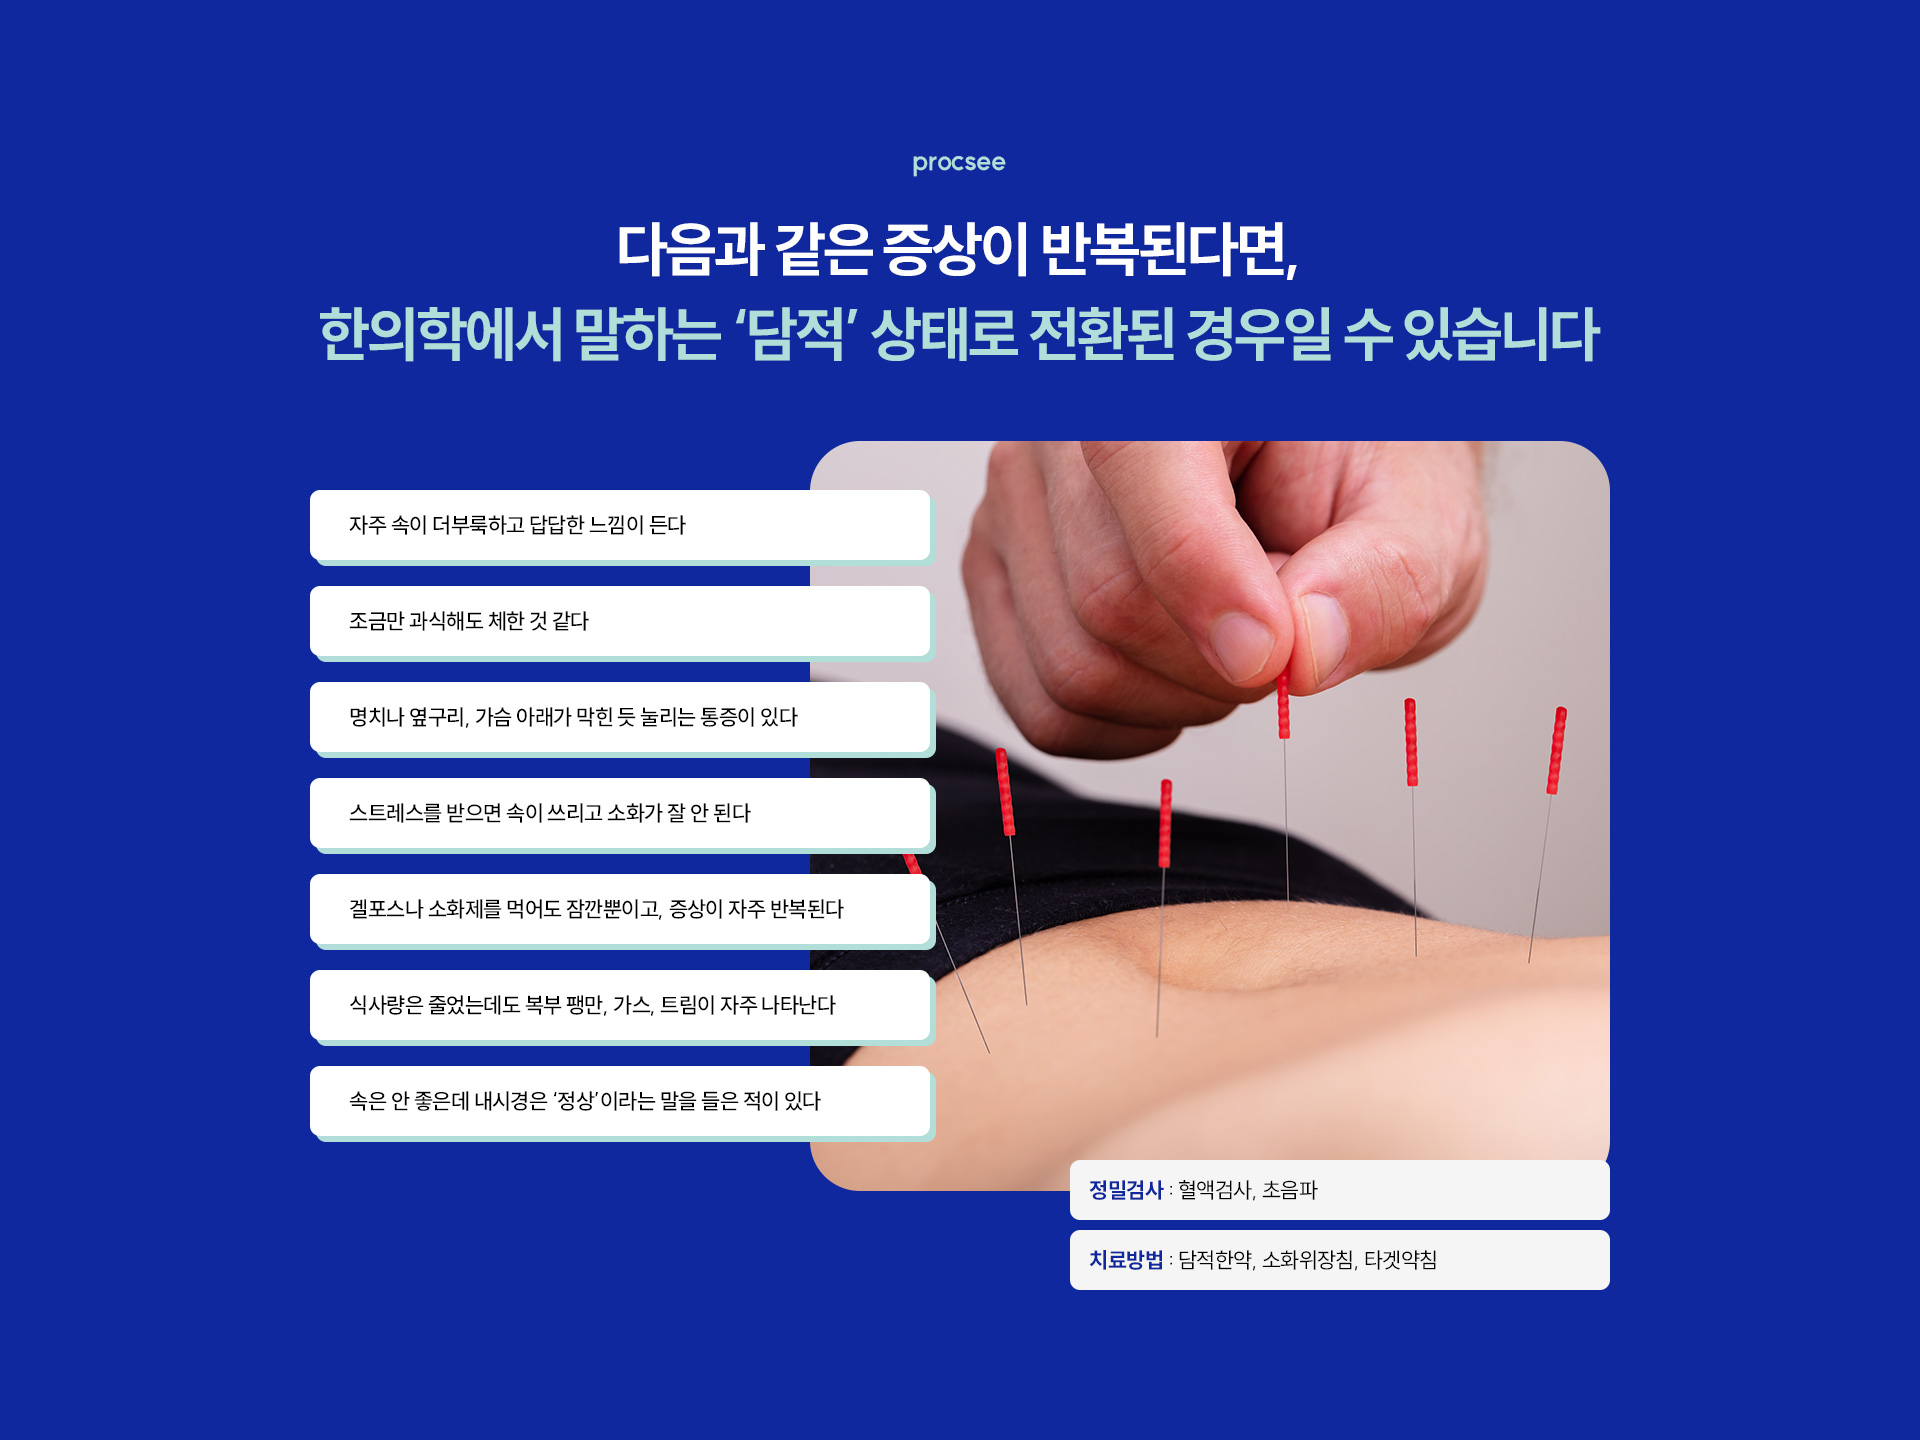

담적·위장 한방 — 내시경 정상인데 속 안 좋은 분 (기운찬 인천)

내시경 정상인데 속 안 좋음, 자주 더부룩, 명치 답답, 복부 팽만, 가스 트림, 소화제 효과 잠깐, 인천 담적 한방, 위장질환 한방, 담적한약, 소화위장침, 타겟약침, 365일 진료, 구월동 위장 한방